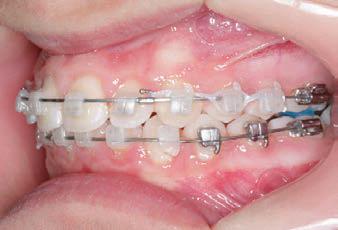

Carriere Motion 3D Appliance

Fastrack your orthodontic treatments. Save 6 months or more.

The SAGITTAL FIRST™ Philosophy is a time-tested approach that standardises, simplifies, and shortens Class II and Class III treatment times. It employs the Carriere Motion 3D Appliance to treat the AP dimension at the beginning of treatment before placing brackets or aligners. By resolving the most difficult part of treatment first, you can achieve a Class I platform in 3 to 6 months, shortening total treatment time by a minimum of 6 months1. You know how excited patients and parents become when you mention shorter treatment times.

CLASS II DIV.1 - Marra

PROVIDED BY: DR. LUIS CARRIÈRE

INITIAL - 4/4/18

PROGRESS 1 - 26/9/18 - Class I platform accomplished in 5.75 months with Motion 3D COLOR Appliance

PROGRESS 2 - 26/9/18 - Placement of the SLX 3D Clear Brackets

[CONTINUED ON NEXT PAGE]

with M-ONE .015 Cu Nitanium 27°

PROVIDED BY: DR. LUIS

PROGRESS 3 - 30/10/18 - With M-TWO .020 x .020 Cu Nitanium 35° archwire

PROGRESS 4 - 27/11/18 - 3 links power chain: 5, 4, bypass 3 to crimp hooks

PROGRESS 5 - 13/3/19 - With M-TWO .020 x .020 Cu Nitanium 35° archwire

PROGRESS 6 - 1/8/19 - With M-THREE.019 x .025 Beta Titanium wire

52 HENRY SCHEIN ORTHODONTICS

FINAL - 10/10/19 - Appliances removed AFTER

PROGRESS 7 - 10/10/19 - Final day in SLX 3D Clear Brackets BEFORE